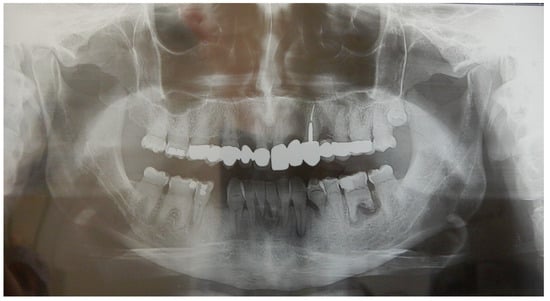

2.1. Patient A

2.2. Patient B

2.3. Father